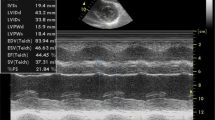

In CA patients, amyloids can deposit in the ventricles, vessels, and valves, leading to wall thickening, left ventricle (LV) volume reduction, biatrial enlargement, and valve thickening. Also, pericardial effusion, pleural effusion, and vena cava dilation are induced by the progression from diastolic dysfunction to restrictive cardiomyopathy [7]. Two typical cases of AL-CA and ATTR-CA are shown in Figs. 1 and 2.

A case presentation of an ATTR-CA patient. A Limb leads electrocardiogram showed low voltage. B Echocardiography showed asymmetric hypertrophy of the LV interventricular septal wall. C, D.99mTc-pyrophosphate quantitative SPECT showed that the radiopharmaceutical uptake was more significant in the heart than ribs. The 1-h and 3-h cardiac mean pixel intensities/rib mean pixel intensities were 2.59 and 2.31, respectively. E, F The positive results of TTR and Congo red stain of myocardial biopsy. G The whole exome sequencing showed c.349G > T in chr18:29,178,543